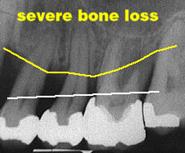

Parodontite severe

mobilitate dentara accentuata pâna la avulsia dintilor

migrari patologice

halena constanta

hiperestezie dentinara datorata denudarii radacinii

pungi parodontale > de 6 mm

resorbtie osoasa accentuata